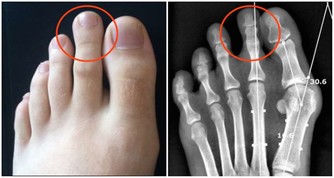

4. 糞便很細,排便不爽

腫瘤一旦變大,就會影響糞便排出,使之變細,且一次不能完全排盡,總感覺想排又排不乾淨。